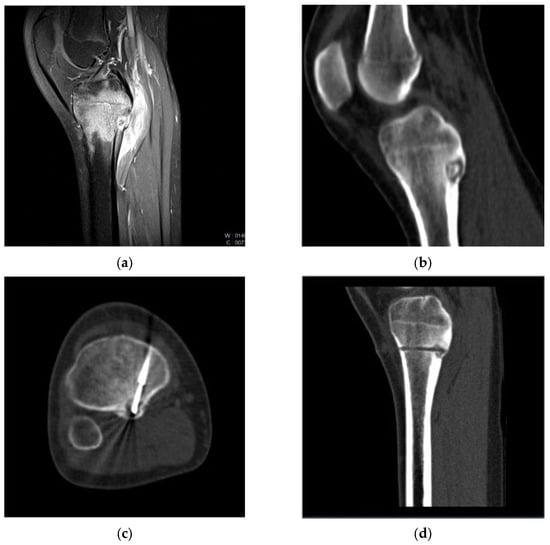

2.2. Procedure